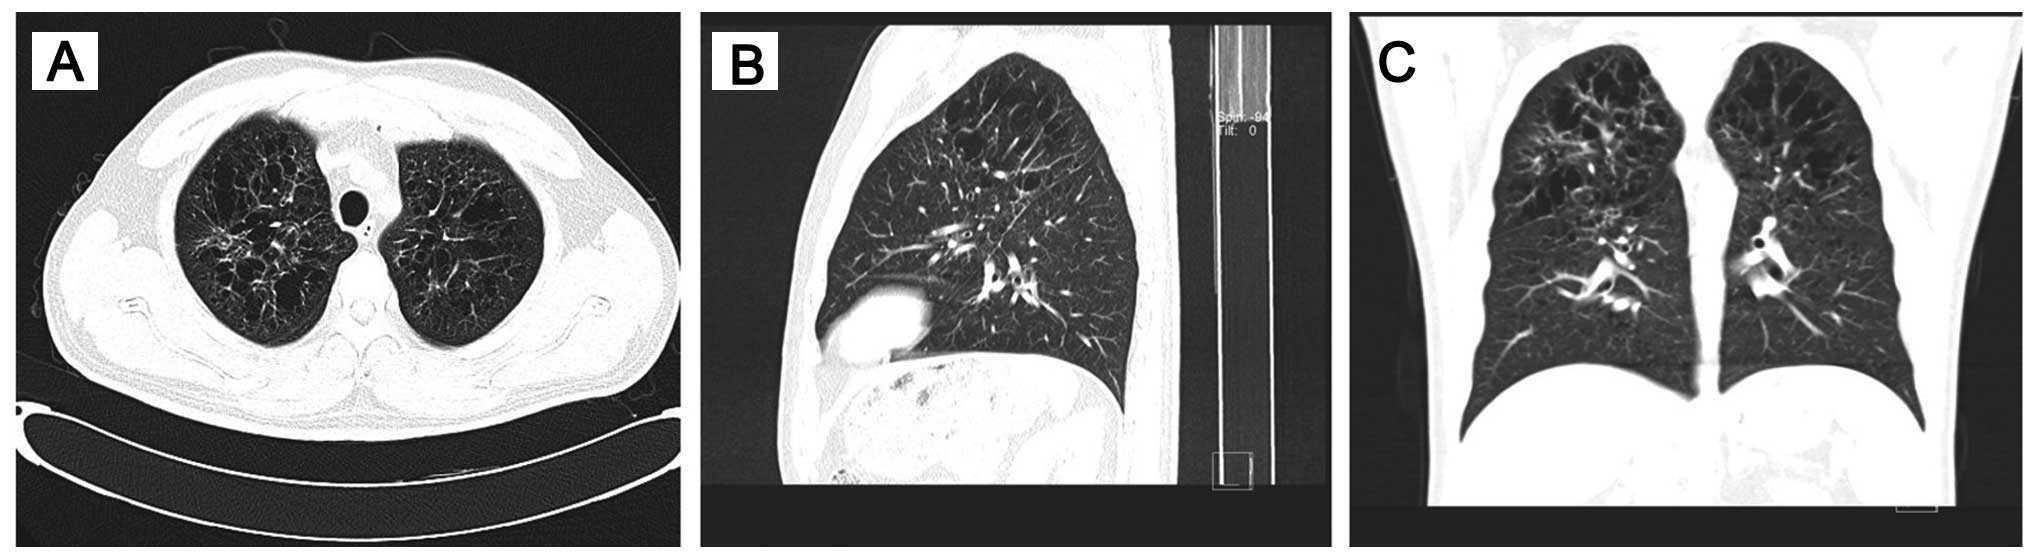

In addition, high-resolution ct (HRCT) of the chest revealed bilateral, diffuse infiltration of the lungs by numerous cysts, mainly distributed in the upper and middle lung fields, while the surrounding pulmonary parenchyma was normal (Fig. 2). A CT-guided percutaneous needle biopsy was performed and the results confirmed the diagnosis of LCH. Histopathologically, a heterogeneous admixture of inflammatory cells, including numerous eosinophils, rare multinucleated giant cells, mononuclear cells and foam cells, was observed (Fig. 3). The histopathological examination revealed proliferation of histiocytes with an infiltration by eosinophils. Immunohistochemically, the histiocytes were S-100+, CD163+, CD1a+, CD68+ (partially), vimentin+, Ki-67+ (~15%) and langerin+. Although the patient was diagnosed with LCH, the aggressive appearance of a destructive lesion on CT images made it necessary to conduct a biopsy in order to establish a definitive diagnosis. there was no evidence of involvement of any other organ on magnetic resonance imaging (MRI) of the head and abdomen. Corticosteroid treatment was administered to the patient. No further treatment was recommended, such as combination chemotherapy, surgery or radiotherapy. Corticosteroid therapy was continued for a few months. There has been no evidence of disease progression during follow-up.

Figure 2.

(A-C) High-resolution computed tomography images showing numerous bilateral pulmonary cystic foci of varying sizes, occasionally with a partially thin or thick cystic wall. Multiple cysts associated with extensive consolidation (with a predominant upper-lobe distribution) were a characteristic feature. The lung involvement in our patient was asymptomatic and diagnosis was confirmed by bone lesion biopsy.